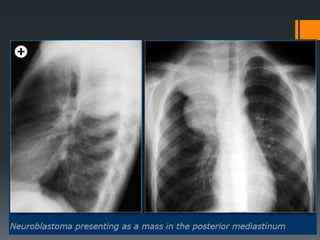

• Malignant thoracictumor of primitive neural crest cells • Tendency to invade into spinal canal via neuroforamina NEUROBLASTOMA Pathology • Most commonly arises from the adrenal gland but can arise anywhere along sympathetic chain, including posterior mediastinum • Third most common pediatric malignancy behind leukemia and central nervous system tumors

• Radiography o Softtissue mass in posterior mediastinum o Rib involvement • Widening of intercostal spaces • Erosion/destruction of ribs o Calcifications: Common (up to 30% by radiography) o Paravertebral soft tissue widening o Bone metastasis • Lucent or sclerotic lesions o Pedicle erosion from intraspinal extension

CT Findings • Posteriormediastinal mass, more commonly in inferior mediastinum but can occur in superior mediastinum/cervical region • Mass often heterogeneous from necrosis, hemorrhage • Calcification seen on CT in up to 85% MR Findings • Heterogeneous in signal and contrast-enhancement • Tends to be high in signal on T2Wl / low in signal on TlWI Ultrasonographic Findings o Heterogeneously echogenic mass

The CT-images showa calcified mass in the posterior mediastinum extending over several vertebrae, which grows into the vertebral canal.